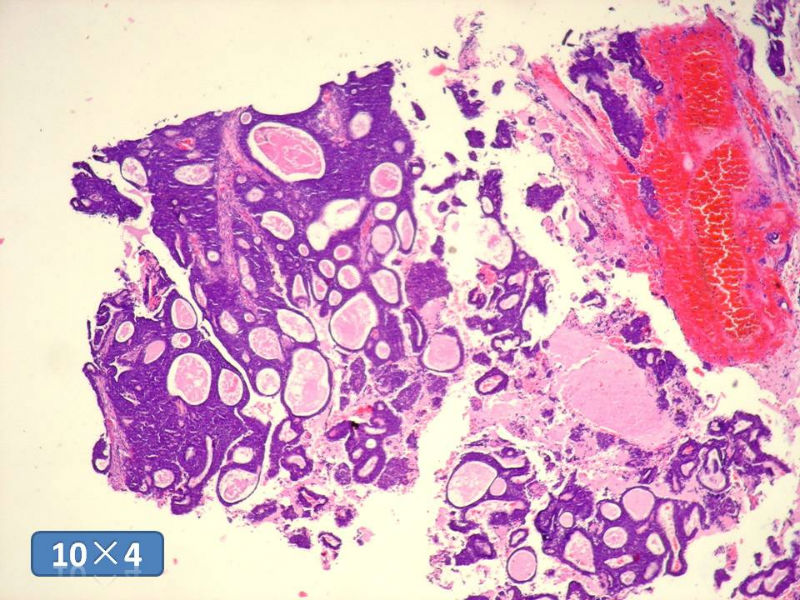

男性,49岁,间断左鼻腔出血3个月。

标签:是嗅母么?

1)嗅神经母细胞瘤?

2)腺肌上皮癌?

3)肌上皮癌?

4)神经内分泌癌?

5)腺样囊性癌?

6)其他?

腺肌上皮癌

感觉要排除畸胎癌肉瘤。

间质为恶性梭形细胞成分,其间感觉是腺体,两种成分密切相关....

免疫组化S-100的阳性区域方式...嗅母可能性大。

支持嗅神经母细胞瘤(伴有腺体分化)

嗅神经母细胞瘤

有上皮和间叶2种结构,畸胎性癌肉瘤是要考虑一下的吧!